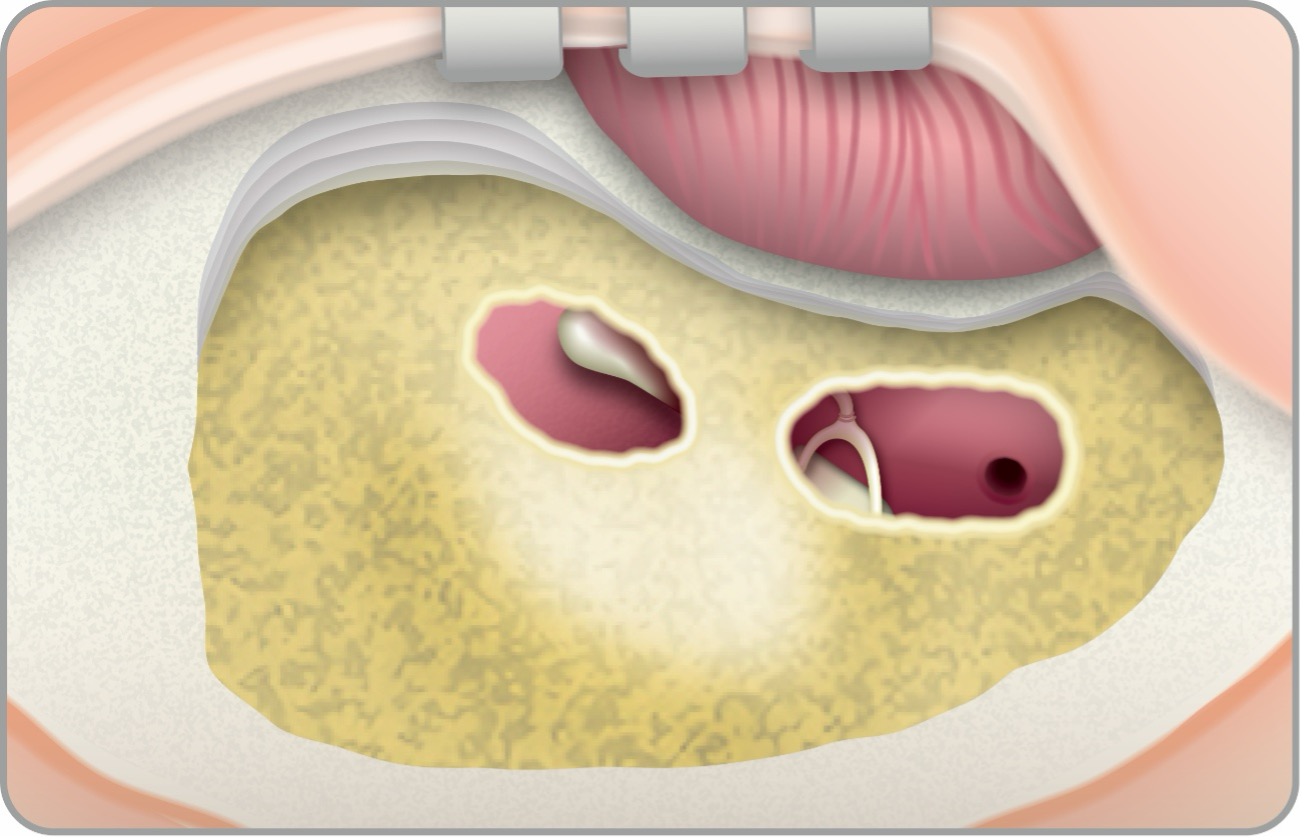

手術方法は、①耳後部の皮膚切開、②乳突削開:乳突洞および乳突蜂巣(Mastoid)の骨削開、③後鼓室開放、④人工内耳電極挿入の順に行います。②以降は通常、顕微鏡や手術用ドリルなどを使用して行われます。